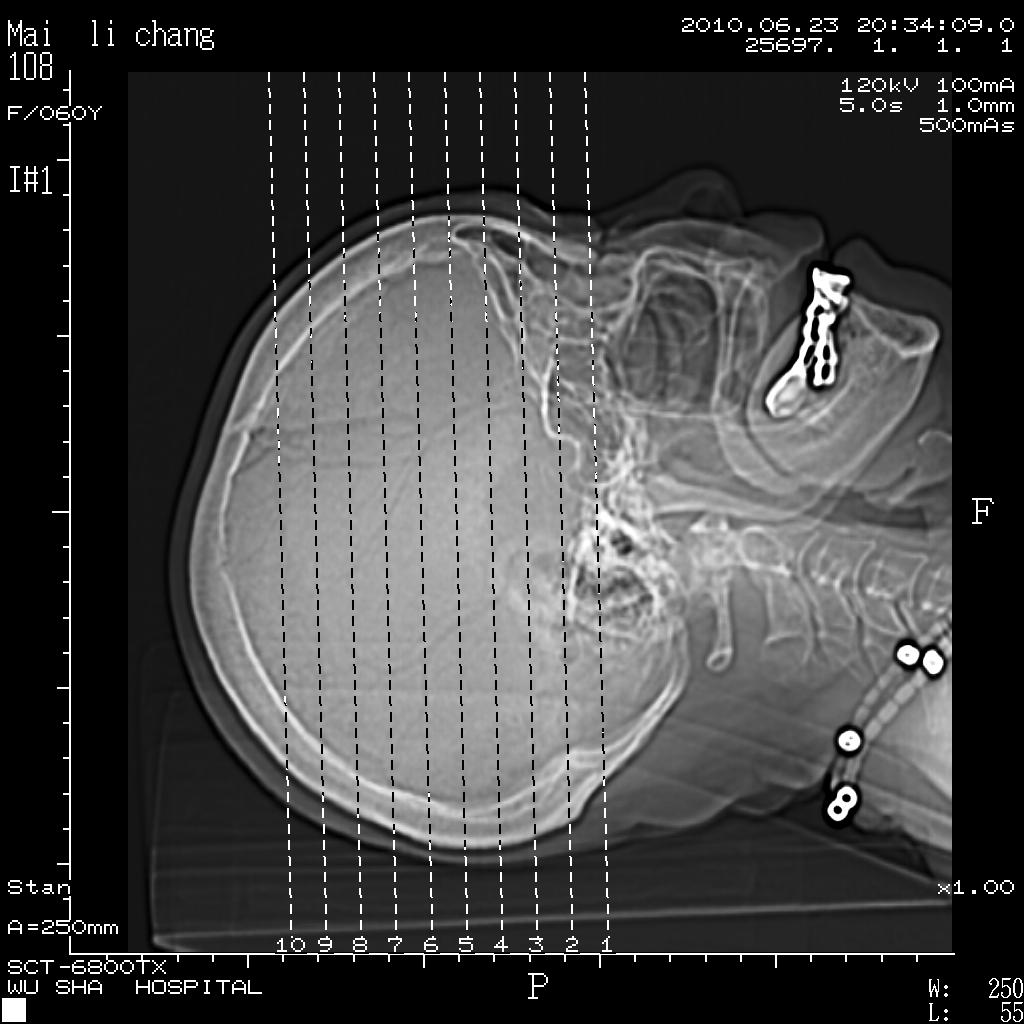

女性,60岁,右手无力一天

结合临床考虑梗塞,但看图片又不太像,面积太大,上下层面太少、